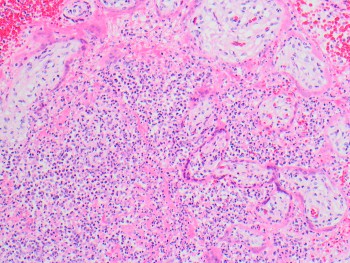

The pattern of inflammation in this placenta is characteristic of placental listeriosis. The pictured H&E stained sections show extensive acute intervillositis with abscess formation, acute necrotizing villitis, and villous necrosis. In many cases of placental listeriosis, there is an accompanying acute chorioamnionitis, which may be quite severe and is often accompanied by bacterial growth in the amnion, although this was not seen in this case.

The differential diagnosis for acute intervillositis includes maternal-fetal sepsis from a variety of other (usually bacterial) organisms. However, in those cases, the acute intervillositis is usually more sparse, usually without abscess formation and villous necrosis, and is more often accompanied by villous agglutination and intervillous fibrin deposition.

The pattern of acute intervillositis with abscess formation in a placenta should raise suspicion for placental listeriosis and prompt a call to notify the clinician caring for the mother. Per the Centers for Disease Control in the United States, listeriosis is nationally notifiable and verified cases must be reported to local, state, territorial, or federal public health authorities.